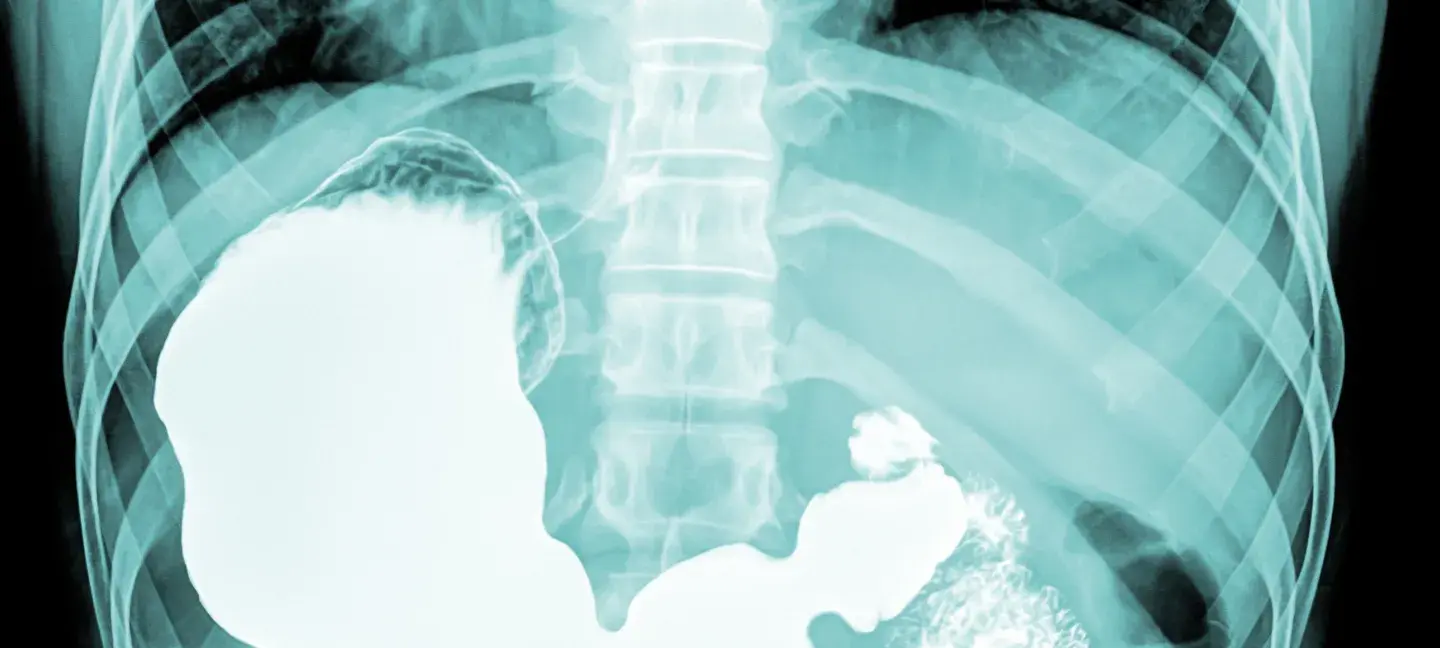

Rontgen - MDL - Maag - Lever - Darm